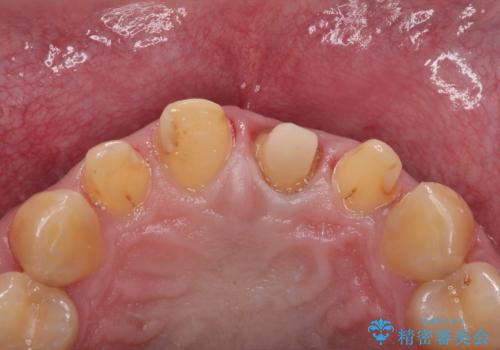

拡大鏡視野下で保険のプラスチック(コンポジットレジン)、虫歯、左上1の被せものを除去し、オールセラミッククラウンに適した形にしました。

歯と歯茎の間に圧排糸と言われる糸を入れてシリコーン印象材にて型どりをしました。